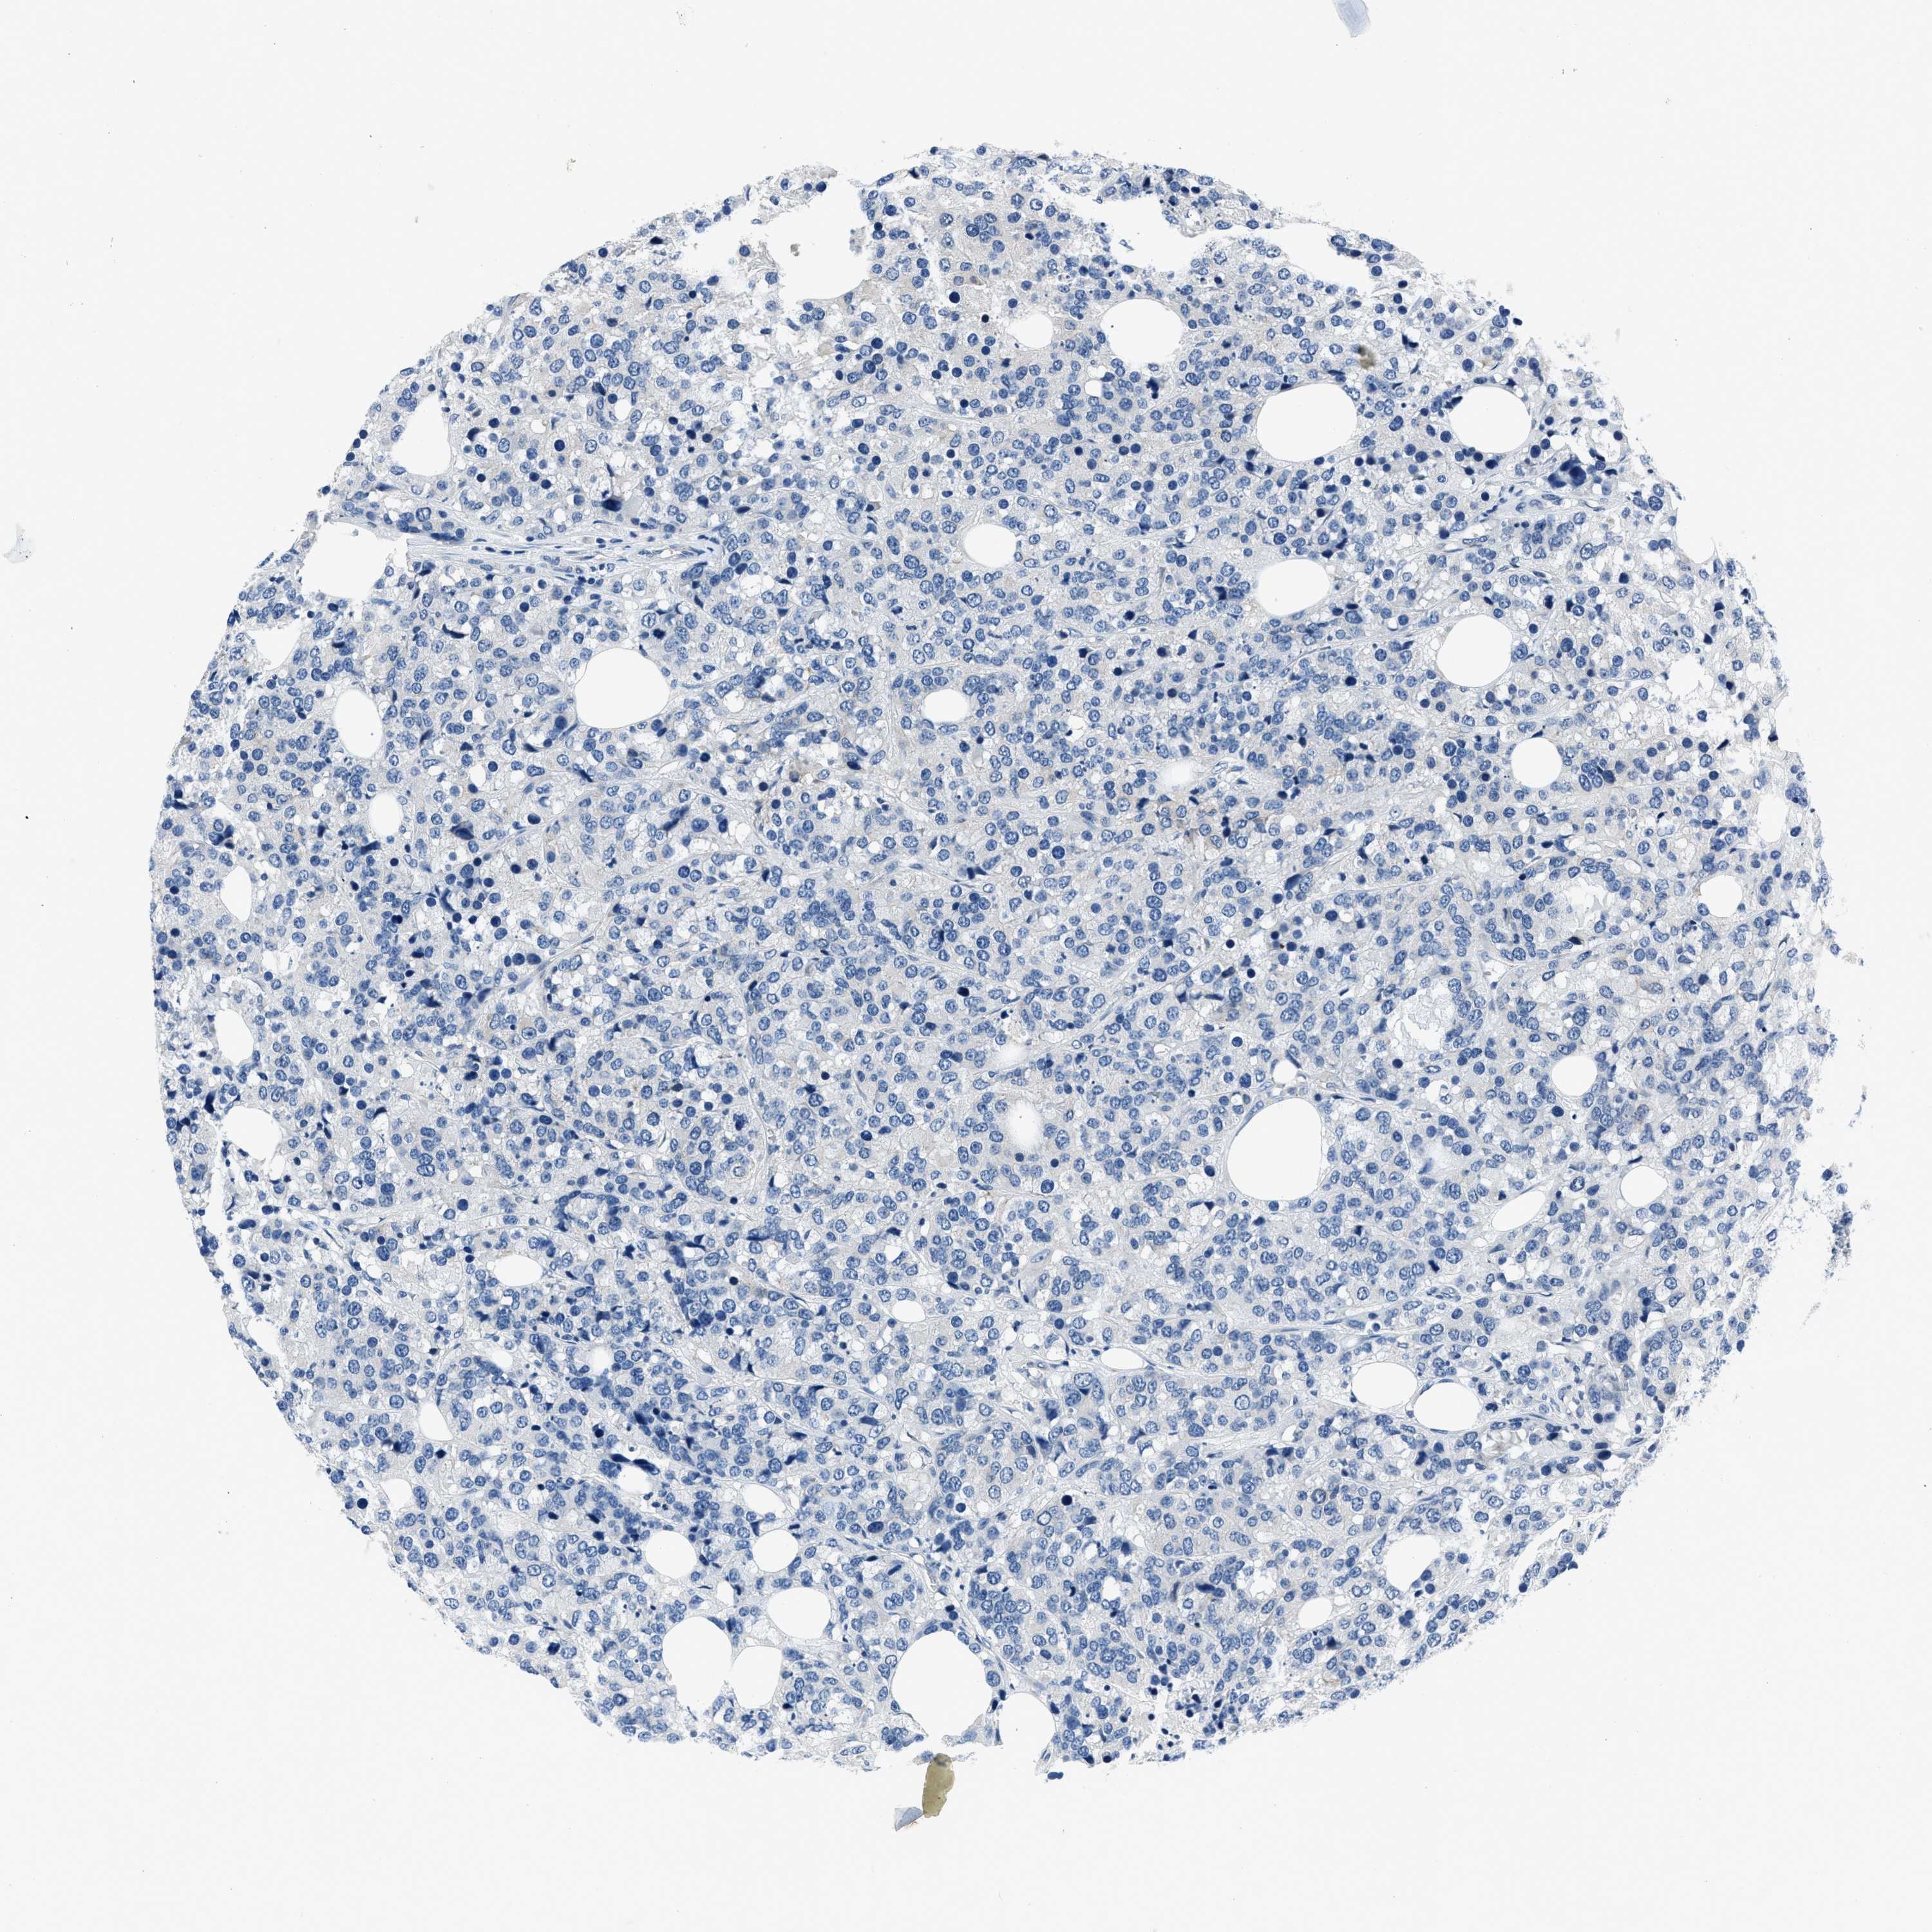

CANCER BREAST CANCER Show tissue menu

BRCA TCGA BRCA VALIDATION PROTEIN EXPRESSION